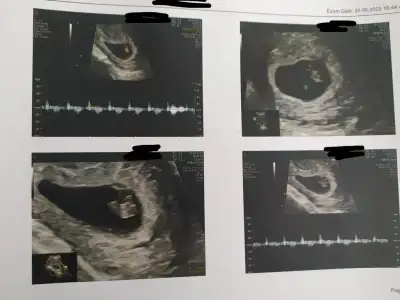

Bizim bebek byle duruyor 18 haftalık oldum ve cinsiyetını öğrenemedim.sizce nedirSelam Kızlarbir çok kişi gruplardan beni bilir. Yine yetiştim imdatlara

5 ve 14. haftaya kadar olan ultrason fotolarınızı paylaşın. Vajinadan mı yoksa karından mı çekildiğini ve kaç haftalık olduğunu da mutlaka belirtin.

görüntüyü biraz uzaktan çeker misiniz10+1 bana da yorum yapabilir misin![]()

görüntüyü biraz uzaktan çeker misiniz

paşa gibi10+1 bana da yorum yapabilir misin![]()

Csnım bakar mısın 9+1 karındanprenses gibi

bu vajina dan mı?